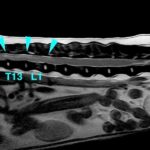

• [MR画像 矢状断像 T2強調画像]

画像で見る病気(飼い主様向け)

#18 頚部脊椎脊髄症(ウォブラー症候群)(飼い主様用)

<症例情報> バーニーズマウンテンドッグ5歳 去勢済みの男の子 主訴:最近首が痛そうで下を…